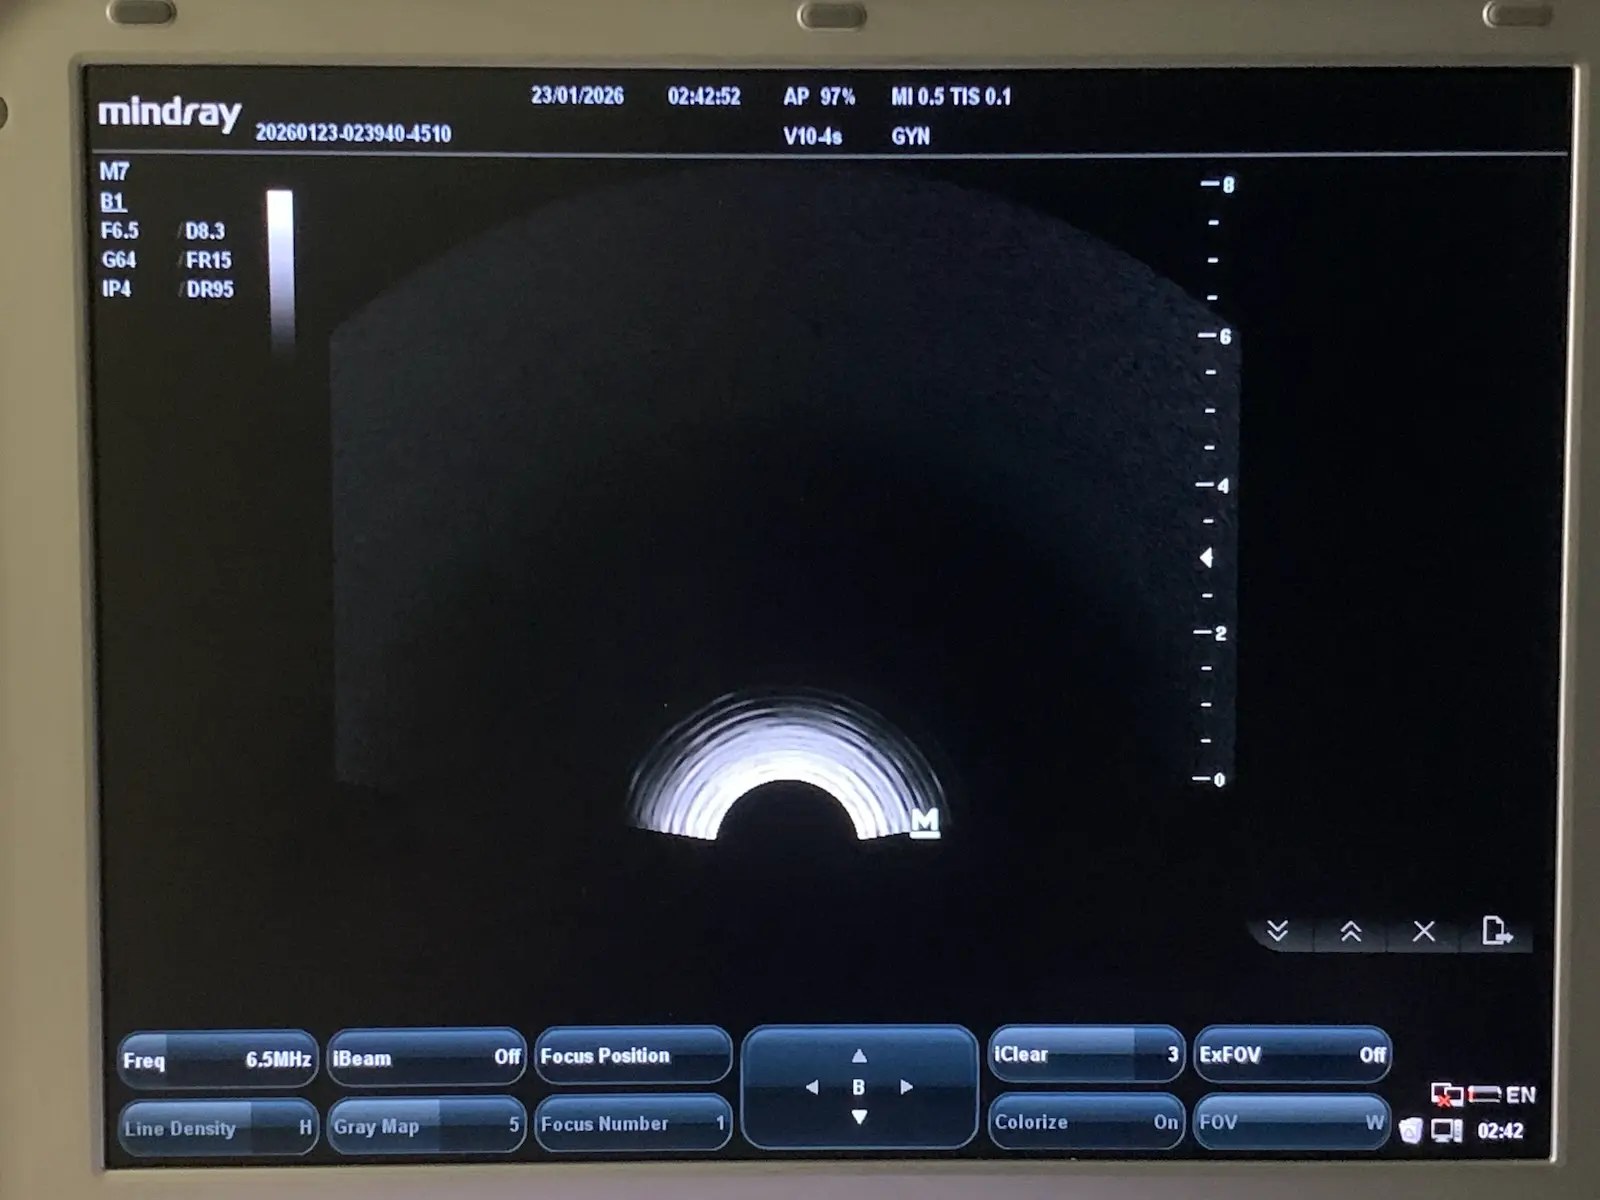

Up for sale is a genuine Mindray V10-4s curved array endocavity probe. This transducer is designed for high-resolution imaging in obstetrics, gynecology, and urology. It features a wide-band frequency range (4–10 MHz) and a small 10mm radius for patient comfort.

Source: Removed from a clinical environment. The probe was tested on a Mindray MR-M7 Ultrasound unit to confirm full functionality, image quality, and connectivity.